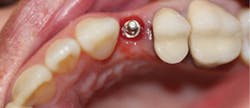

Figure 12: Final crown seating

Figure 13: Two-year follow-up

A 1.8 mm x 14 mm Anew implant (Dentatus) was selected, and a surgical guide was fabricated for a flapless approach. In this instance, a healing cap was placed, and the existing flipper was relieved to address financial concerns (figures 9 and 10). A screw-retained crown was fabricated three months post insertion (figures 11 and 12). The patient reported no postoperative discomfort, and the case remains successful, as shown in the two-year postoperative x-ray (figure 13).